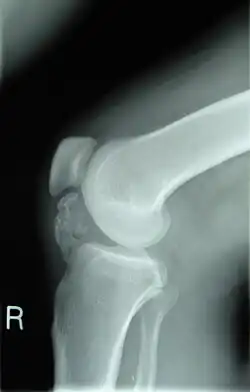

| Lateral radiograph of the knee demonstrating ossification in the peritendinous tissues in a patient with osteochondroma. | |